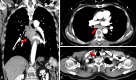

Mediastinal tuberculous lymphadenitis rarely mimics esophageal submucosal tumor, particularly in the case of multidrug-resistant tuberculosis (MDR-TB). Herein, we report the case of a 61-year-old woman who visited a local hospital complaining of odynophagia. An initial esophagogastroduodenoscopy revealed an esophageal submucosal tumor, and subsequent chest computed tomography showed subcarinal lymphadenopathy with an esophagomediastinal fistula. The patient was then referred to Samsung Medical Center, and a second esophagogastroduodenoscopy showed deep central ulceration, as well as a suspicious fistula in the esophageal submucosal tumor-like lesion. A biopsy examination of the ulcerative lesion confirmed focal inflammation only. Next, an endobronchial, ultrasound-guided lymph node biopsy was performed, and TB was confirmed. The patient initially began a course of isoniazid, rifampicin, ethambutol, and pyrazinamide. However, after a drug sensitivity test, she was diagnosed with MDR-TB, and second-line anti-TB medications were prescribed. She recovered well subsequently.